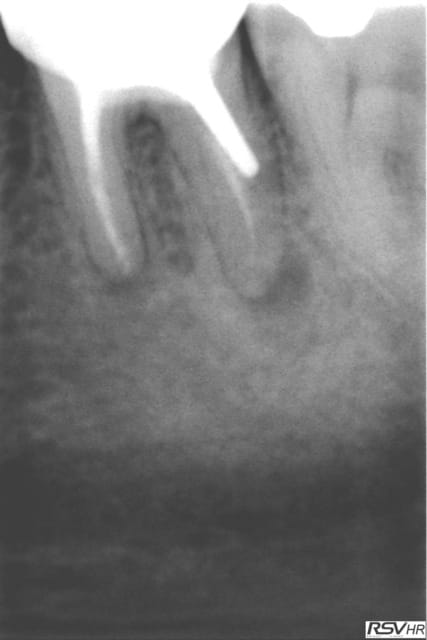

Cas pratique au S1, R25. Couronne déscellée à la base. Temps identique à une endo classique.

Digue inutile en antérieur.